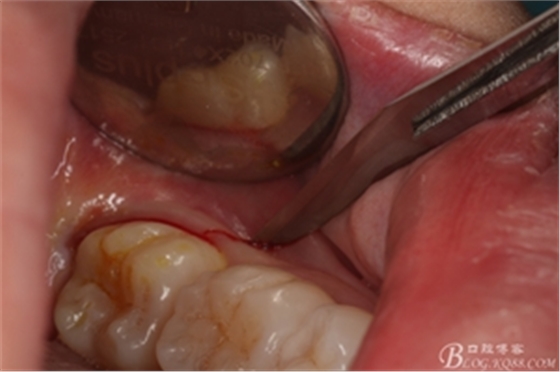

圖1.術(shù)前的口內(nèi)照片:38未萌出、牙齦輕度紅腫,37遠(yuǎn)中有盲袋。

圖6.麻醉效果確定后,在37的近中做垂直松弛切口+遠(yuǎn)中水平切口

圖7. 遠(yuǎn)中的水平切口